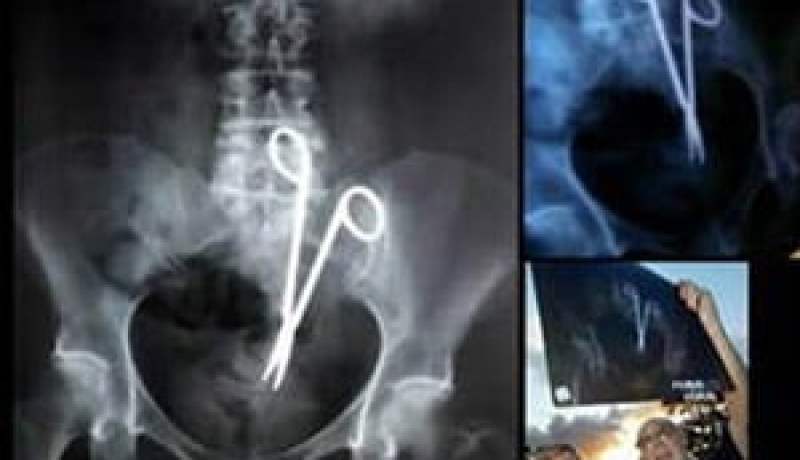

احصاء ما بين 350 و 500 شكوى خلال السنتين الأخيرتين:عقوبة الطبيب المخطىء قد تصل إلى 5 سنوات سجنا إذا ثبت إهماله

أكد قصاب مصطفى، نائب رئيس المجلس الوطني لأخلاقيات الطب، تسجيل ما بين 350 و500 شكوى خلال السنتين الأخيرتين على المستوى الوطني ضد أطباء لدواعي تتعلق بالخطأ الطبي.

وفي هذا السياق، أوضح المحامي، عمار خبابة، في اتصال بـ “النهار” أن عقوبة الطبيب الذي يتسبب في خطأ طبي للمريض تختلف باختلاف الضرر الذي لحق بهذا الأخير، مؤكدا أن العقوبة تتراح بين شهرين و 5 سنوات حبسا، إما نافذ أو غير نافذ، كما قد يمنع الطبيب المخطئ، حسب نفس المصدر، من ممارسة المهنة إما مؤقتا أو نهائيا في حالة أكدت الخبرة الطبية التي يتولاها المجلس الوطني لأخلاقيات مهنة الطب، وقوع خطأ أو إهمال ألحق الضرر بالمريض، هذا ويضيف الأستاذ خبابة أن الطبيب في هذه الحالة ملزم بدفع تعويض للمريض المتضرر.